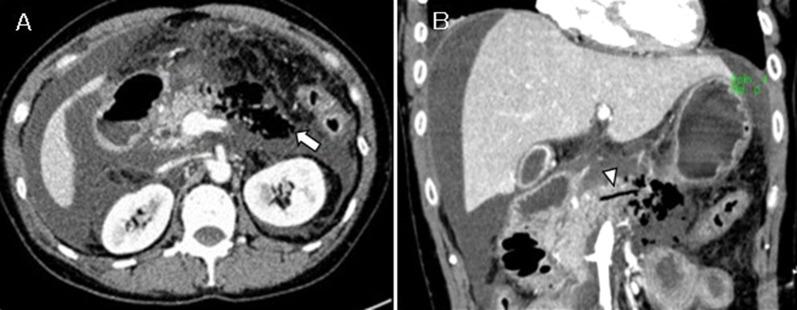

Case 1: A 76-year-old man was referred to our hospital after being diagnosed with acute pancreatitis. At post-admission, his abdominal symptoms worsened, and a repeat CT scan revealed increased retroperitoneal gas. Due to the high risk for gastrointestinal tract perforation, emergent laparotomy was performed. Fat necrosis was observed on the anterior surface of the pancreas, and a diagnosis of acute necrotizing pancreatitis with retroperitoneal emphysema was made. Thus, retroperitoneal drainage was performed. Case 2: A 50-year-old woman developed anaphylactic shock during the induction of general anesthesia for lumbar spine surgery, and peritoneal irritation symptoms and hypotension occurred on the same day. Contrast-enhanced CT scan showed necrotic changes in the pancreatic body and emphysema surrounding the pancreas. Therefore, she was diagnosed with acute necrotizing pancreatitis with retroperitoneal emphysema, and retroperitoneal cavity lavage and drainage were performed. In the second case, the intraperitoneal abscess occurred postoperatively, requiring time for drainage treatment. Both patients showed no significant postoperative course problems and were discharged on postoperative days 18 and 108, respectively.